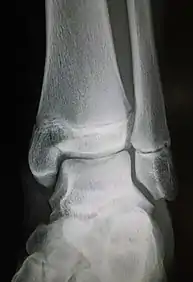

Ankle radiographs are used to detect widening of the tibiofibular syndesmosis or medial clear space. The medial clear space is the area between the talus of the ankle and the medial malleolus. Damage to the deltoid ligament and syndesmotic ligaments result in mortise instability, causing the talus to laterally shift and widen the medial clear space.[4][12] A clinical study, conducted in 2006 and published in the Journal of Bone and Joint Surgery, found that the medial clear space size of a normal ankle and an injured ankle measured at 4 millimetres and 5.4 millimetres in length respectively.[11] To confirm diagnosis, full-leg radiographs are used to inspect for fractures of the proximal fibula and widening of the interosseous clear space (or tibiofibular clear space). The interosseous clear space is the area between the medial side of the fibula and lateral side of the tibia. A peer-reviewed study, published in Injury in 2004, found that an interosseous clear space greater than 10 millimetres indicates diastasis of the syndesmotic ligaments.[4]

If necessary, Computed Tomography (CT) or Magnetic Resonance Imaging (MRI) may also be used to clarify diagnosis. MRI scans can check for interosseous membrane or tibial tubercle damage if high instability of the ankle is diagnosed.[8][11] Arthroscopy may be used to diagnose a syndesmotic lesion but is often not recommended due to operative difficulty.[13] Stress radiographs of the ankle are used to assess the integrity of the deltoid ligament and tibiofibular syndesmosis.[9][13] The size of the medial clear space can also be measured using stress radiography.[11]